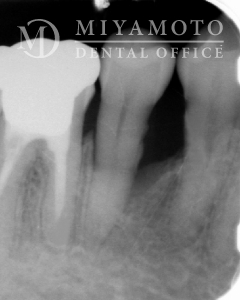

症例14

リグロス®を用いた歯周組織再生療法

1. 治療前

2. 治療後